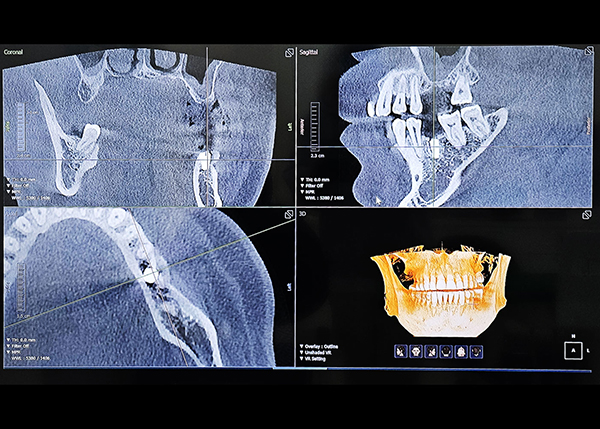

3D 수술 가이드를 통한

오차 없는 초정밀 수술

네비게이션 디지털 임플란트

3D CBCT와 최신 디지털 스캐너를 이용해 채득한 구강 데이터를 기반으로 3D 모의수술 후 맞춤 제작된 수술 가이드를 사용해 미리 계획된 위치에 오차 없는 정확한 식립이 가능하기 때문에 고난이도 임플란트 케이스도 적용 가능하며, 최소침습으로 수술 시간이 짧고 체력적으로 부담이 적습니다.

3D CT&스캐너 디지털 정밀 진단

• 일반 임플란트 치아 상태 및 신경의 위치를 2D(평면)으로만 확인이 가능해 정확한 진단이 어려울 수 있음

• 3D CT를 통한 컴퓨터 분석 현재 턱 뼈와 잇몸의 상태를 3차원 입체 영상으로 확인이 가능해 정밀 진단에 따른 오차 없는 수술이 가능